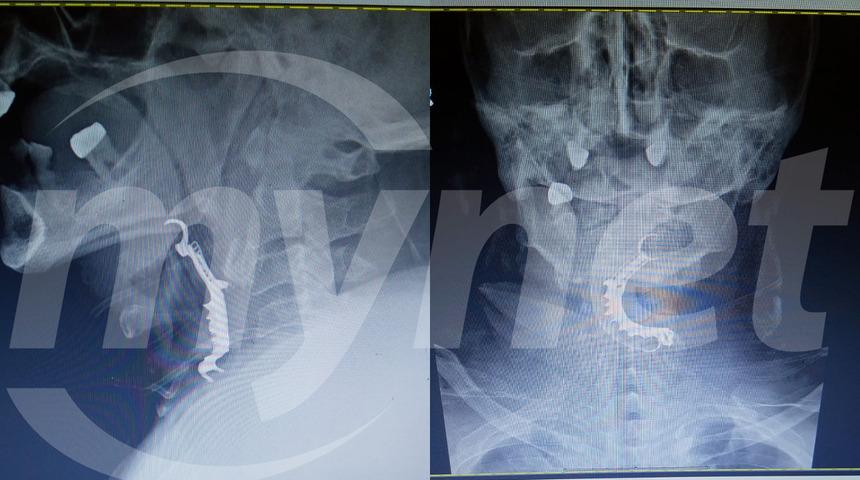

Hastanede hazırlanan raporda ise, hastanın ağzından ve öksürürken kan geldiği kayda alınmış. Raporun devamında hastanın ağzında yabancı cisim olduğu şüphesiyle grafi çekildiği bunun sonucunda da hastanın boğazına takma dişlerinin kaçmış olduğu görüldüğü yazıyor. Ancak iddialar bununla da sınırlı değil. Hastanın oğlu Kadir K'nın iddiasına göre hastane raporda değişiklik yapmış ve suçu örtbas etmeye çalışmış.